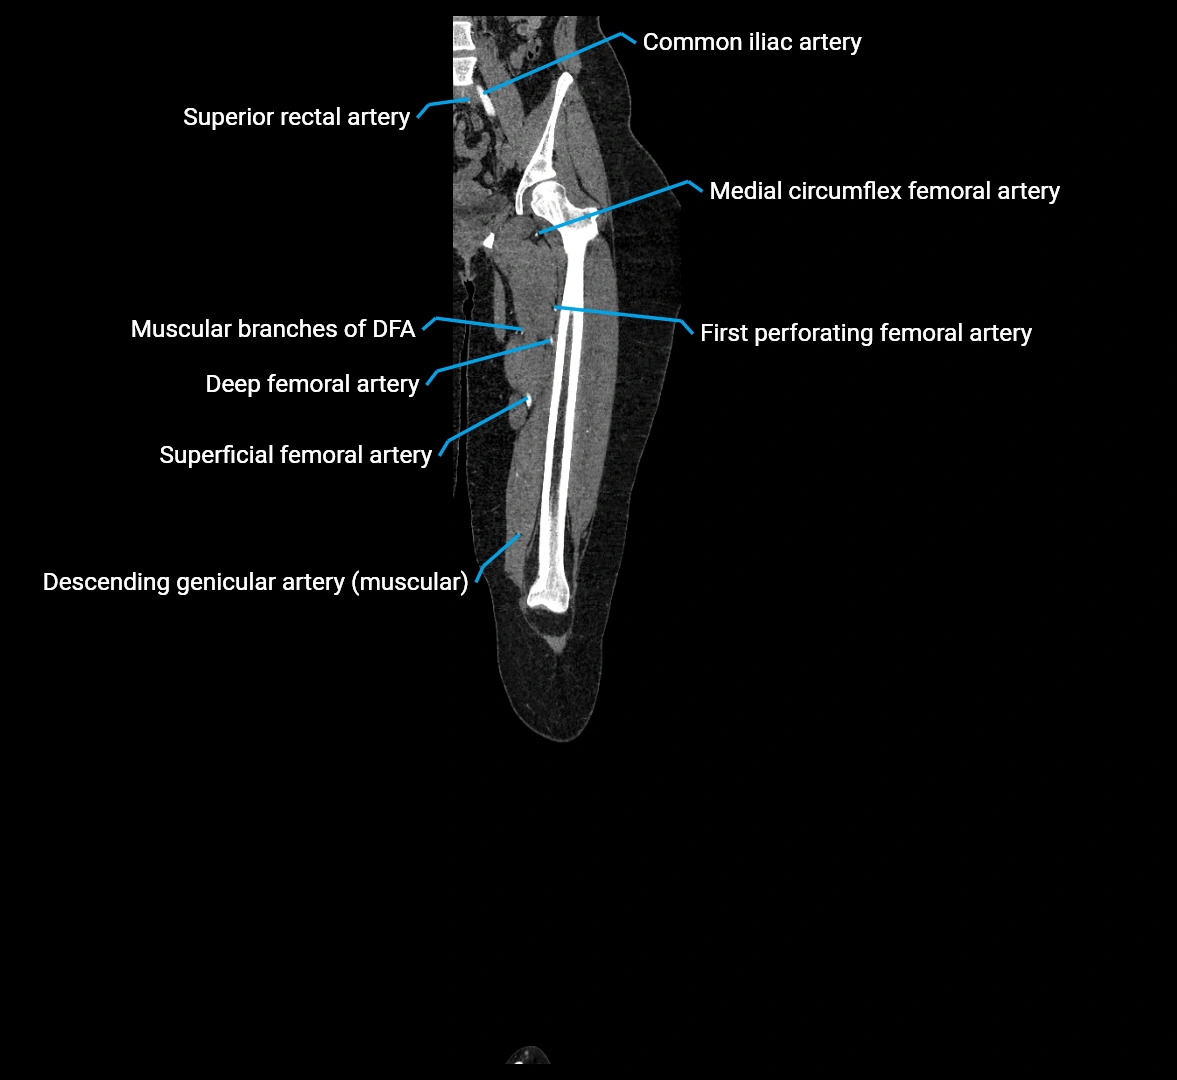

CT images

image

Contrast-enhanced CT (CTA):

• Gold standard for abdominal aortic imaging

• Provides excellent detail of lumen, wall, aneurysm, thrombus, and branch vessels

• Multiplanar and 3D reconstructions help in aneurysm measurement, stent graft planning, and dissection evaluation

• Terminal branches: right and left common iliac arteries